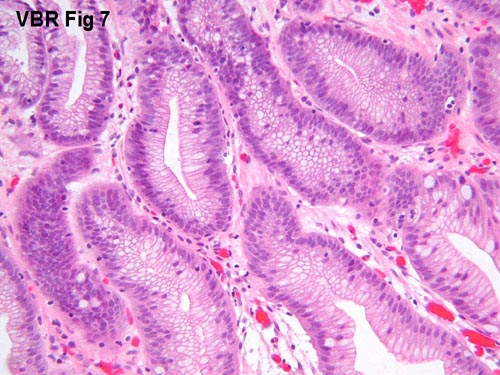

Fig 7. Gastric biopsy from a patient with gastric ulcer syndrome

(20x objective lens).